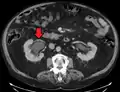

Left sided hydronephrosis in a person with an atrophic right kidney. Stent is also present (image below).

Left sided hydronephrosis, coronal view. Stent is also present.

Treatment of hydronephrosis focuses upon the removal of the obstruction and drainage of the urine that has accumulated behind the obstruction. Therefore, the specific treatment depends upon where the obstruction lies.[12]

Acute obstruction of the upper urinary tract is usually treated by the insertion of a nephrostomy tube. Chronic upper urinary tract obstruction is treated by the insertion of a ureteric stent or a pyeloplasty.[11]